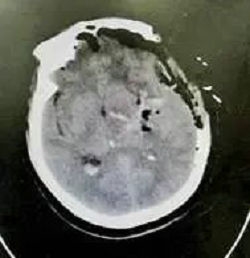

完善术前准备后,周少龙博士主刀手术。在内镜的直视下,将脑扩张器缓慢进入血肿中心,最大限度的减少副损伤,通过调整不同角度,基本清除了所有血肿,并用双极电凝在内镜直视下止血。术后患者病情平稳,复查CT显示颅内血肿清除彻底。

术后CT显示血肿清除彻底